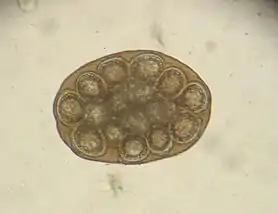

Les anneaux gravides de l'adulte, fixés dans l'intestin grêle du carnivore, l'hôte définitif, libèrent dans la lumière des œufs sphériques, réunis par groupe de 10 à 12 dans des capsules ovigères qui sont rejetées dans le milieu extérieur avec les matières fécales.

Il se fait par découverte dans les selles des capsules ovigères et se trouve bientôt confirmé par l'expulsion du ver.